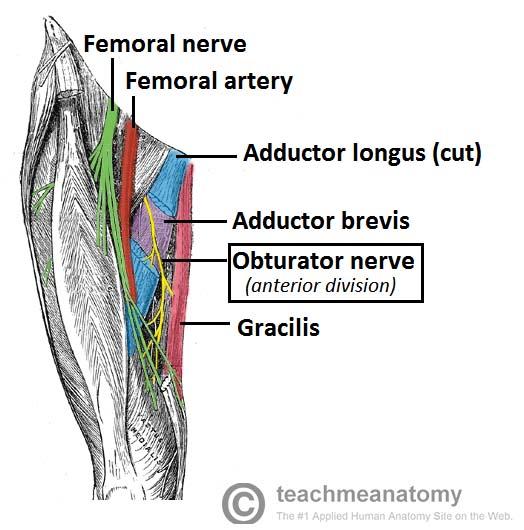

What is the path of the obturator nerve?

runs medial to psoas major in pelvis

enters medial thigh through obturator foramen

splits into deep and superficial branches at adductor brevis

Which muscles are innervated by the obturator nerve?

anterior and posterior branches?

all medial thigh muscles: gracilis, pectinius, adductor longus, adductor brevis, and adductor magnus (adductor part)

posterior branch is adductor magnus

anterior branch is to all other muscles

origin course and distribution of obturator n

O L2-L4

C descends along medial border of psoas and enters thigh through obturator foramen through with obturator artery and vein. divides into anterior and posterior branches that straddle adductor brevis.

D medial muscles of thigh except hamstring part of adductor magnus

origin and distribution of anterior branch of obturator nerve

O obturator n

D adductor longus, brevis, gracilis and pectineus

origin and distribution of posterior branch of obturator nerve

O obturator n

D obturator externus and adductor magnus (adductor part)